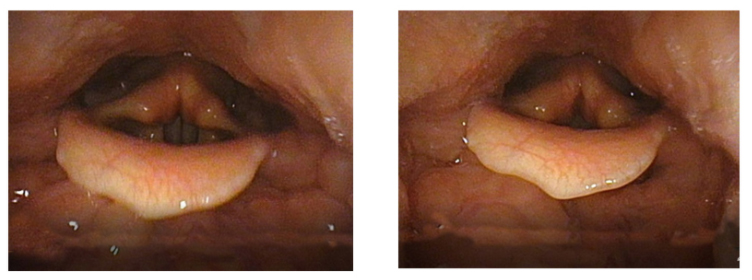

Image 5a & 5b

Images 5a and 5b are Garcia’s pictures. They are not exactly the same as Stark’s. Image 3a shows the opened glottis and Image 3b shows the closed glottis without explaining which part is vibrating during the phonation. However, in 1855, Garcia indicated an explanation similar to Stark’s: “This deep contact, which continues even after the apophyses no longer partake in the vibrations, gives a deep tension to the membranes, increases the depth of their contact, and, as a necessary consequence, augments the resistance they present to the air.”[34] To my understanding, Garcia explains that the arytenoid cartilages are not vibrating during the phonation, although he does not say here if this is unique to the case of Coup de la Glotte. In 1847, before his invention of the laryngoscope, Garcia explains that the glottis lips may still vibrate “either when the posterior extremities are put into contact (by bringing together of the internal processes of the arytenoids), or when these extremities remain separated. In the first case, the sounds are emitted with all the brilliance possible; in the second, the voice takes a dull character.”[35]

The experimental component of this research suggests that the technique of Coup de la Glotte may function better when used in conjunction with the technique of Voix Blanche. The glottis filming indicates that Coup de la Glotte tends to constrict and narrow the vocal tube. The pharynx is pressed inwards and the larynx tends to place itself in a slightly higher position.

Image 11 & 12: The filming was made by Inselspital Bern

Image 11 illustrates the onset of F5 without Coup de la Glotte. Image 12 illustrates the exact moment of onset of F5 with Coup de la Glotte. When the onset is executed whith Coup de la Glotte the pharynx muscles presses inwards, narrowing the vocal tube. The constriction even seems to push the larynx slightly upwards. It may be possible to train the larynx to stay fixed in low position when executing Coup de la Glotte, although this experiment suggests that it naturally rises. This indicates that the technique of Coup de la Glotte best suits the high larynx position, not a fixed lowered larynx which Stark and Austin claim to be Garcia’s intention.[75] The Coup de la Glotte causes a slim, narrow vocal tube. The wideness of the vocal tube affects the formants and, consequently, the timbre. Garcia claimed that the Coup de la Glotte gives stability to the tone and phrase. This narrow timbre, as illustrated in the middle of image10, was probably his vocal ideal.